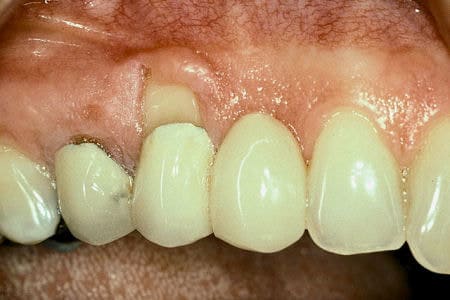

Before

Patient: Jill